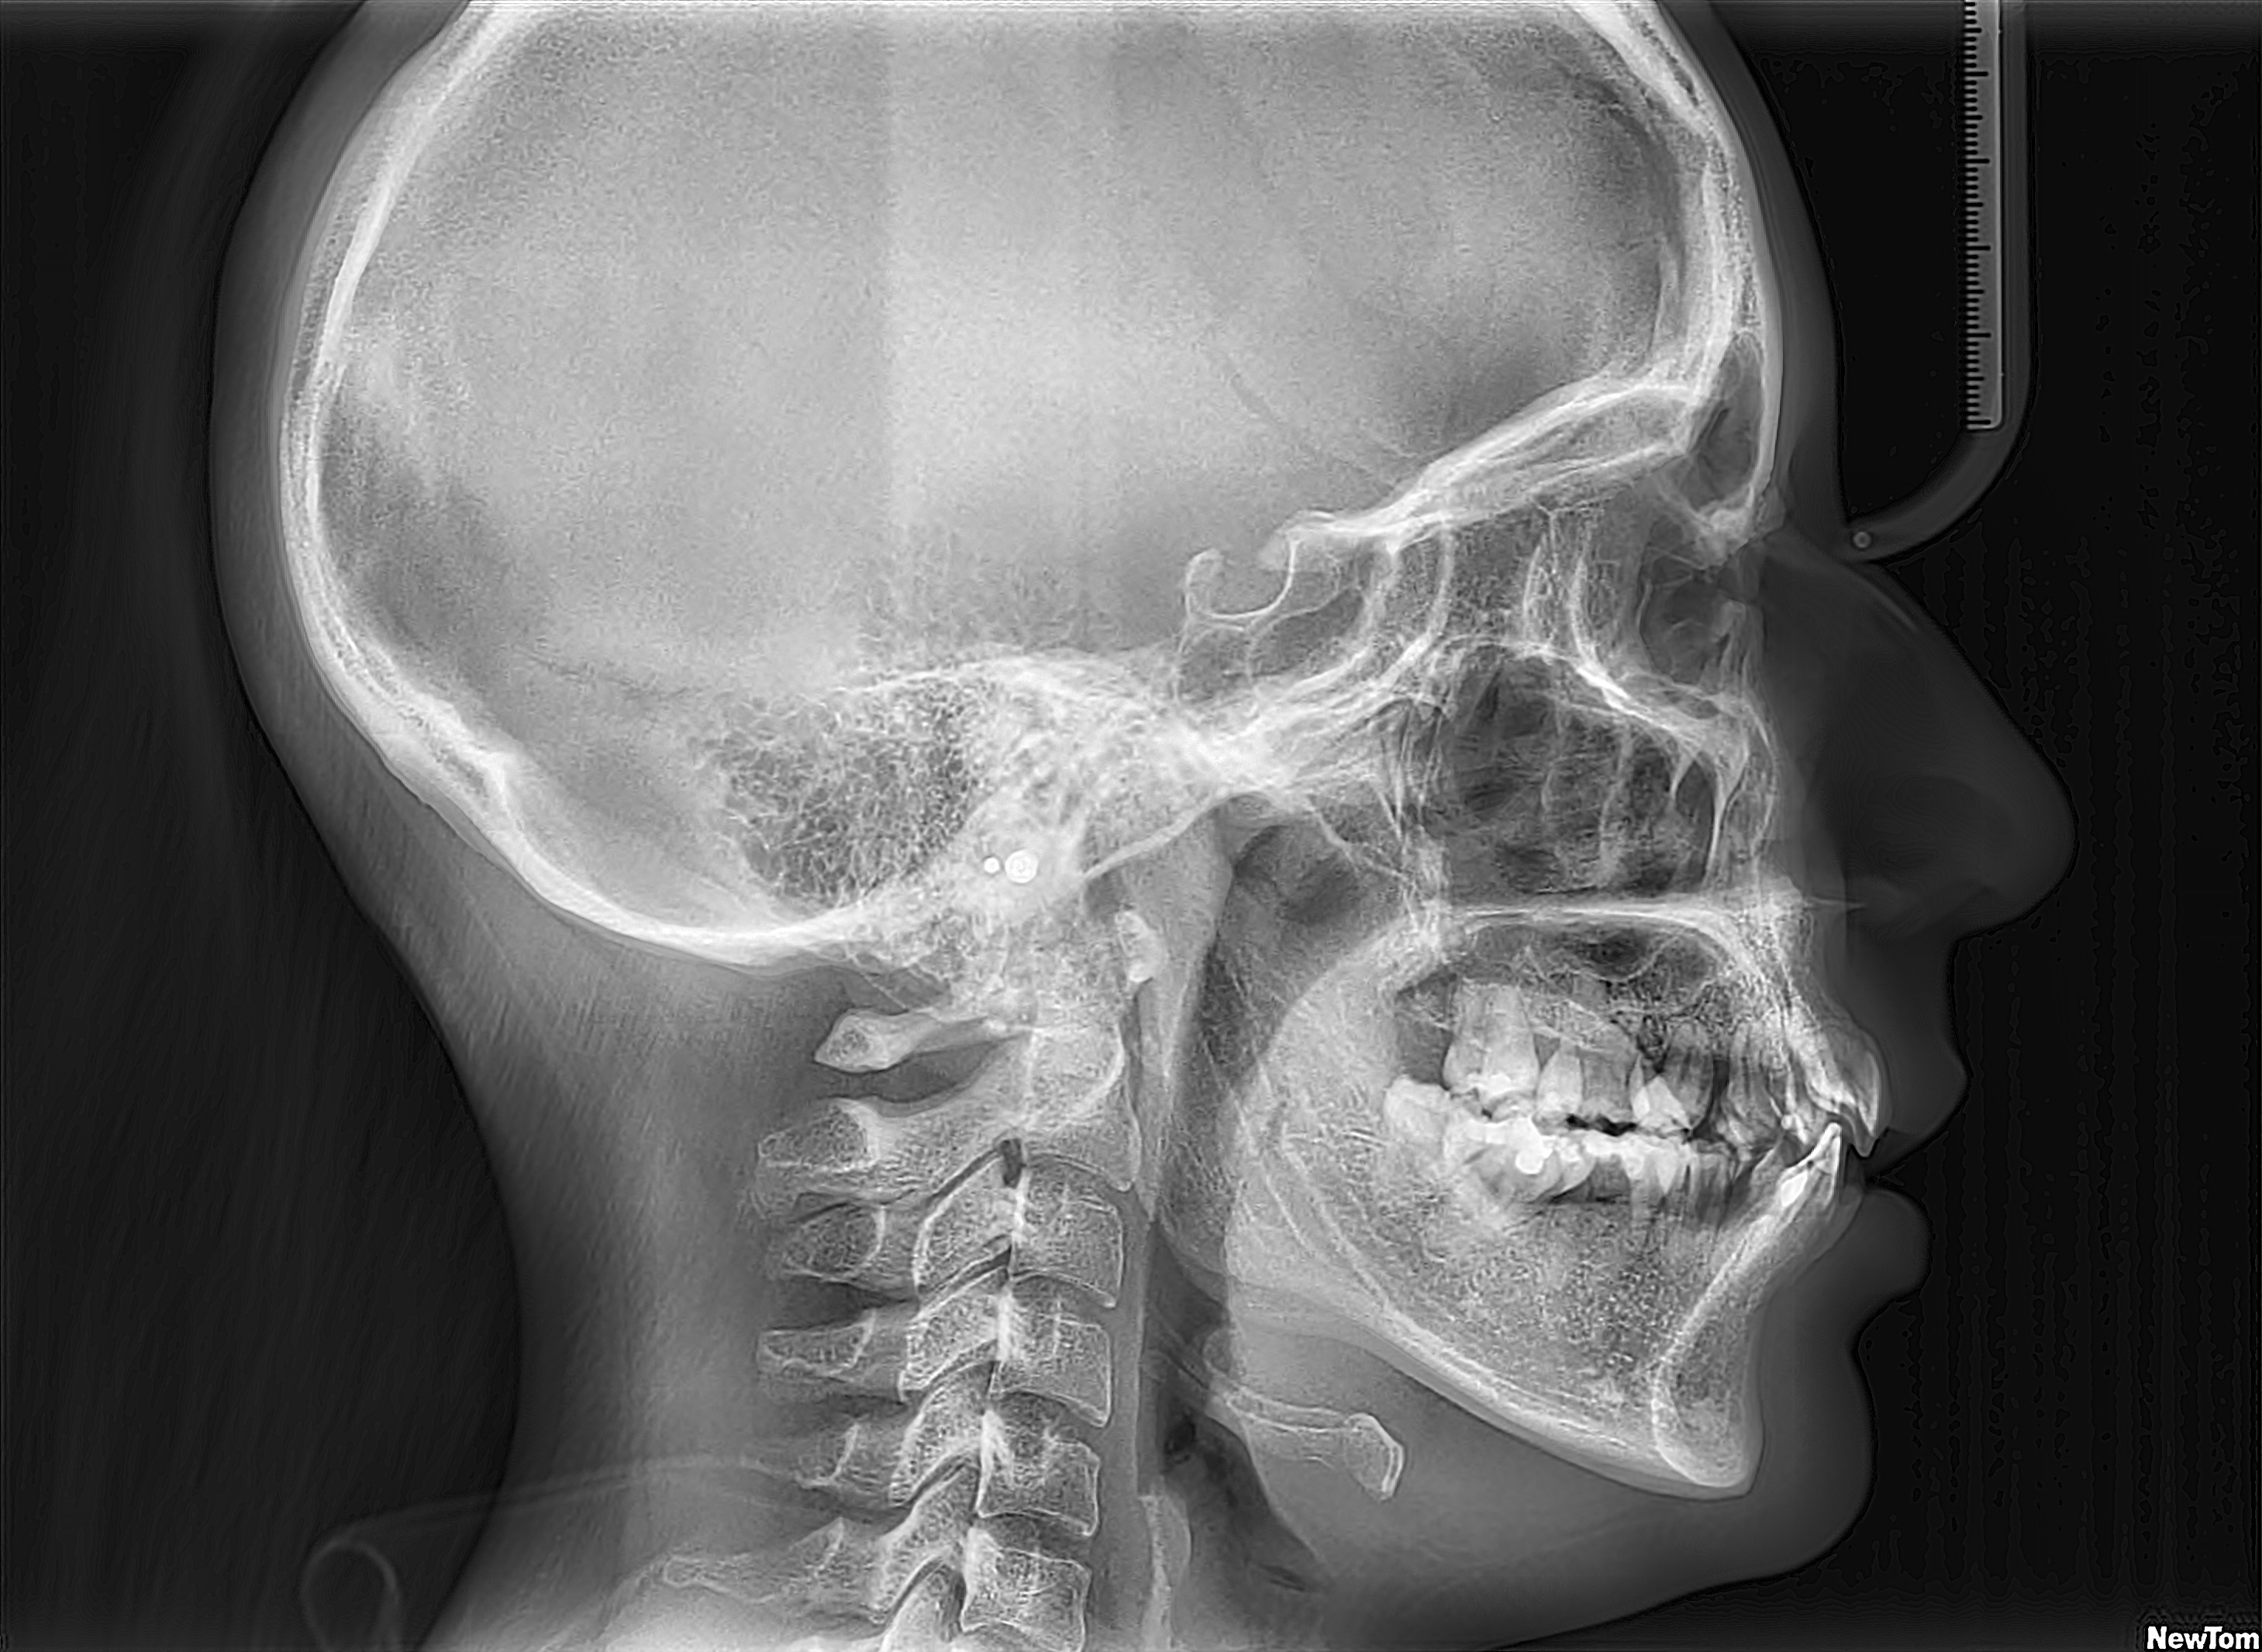

Telerradiografía Lateral

Evalúa el perfil del paciente, sus tejidos blandos y óseos. Es habitual en estudios de ortodoncia, patologías en cráneo, mandíbula, cervicales y cirugía ortognática.